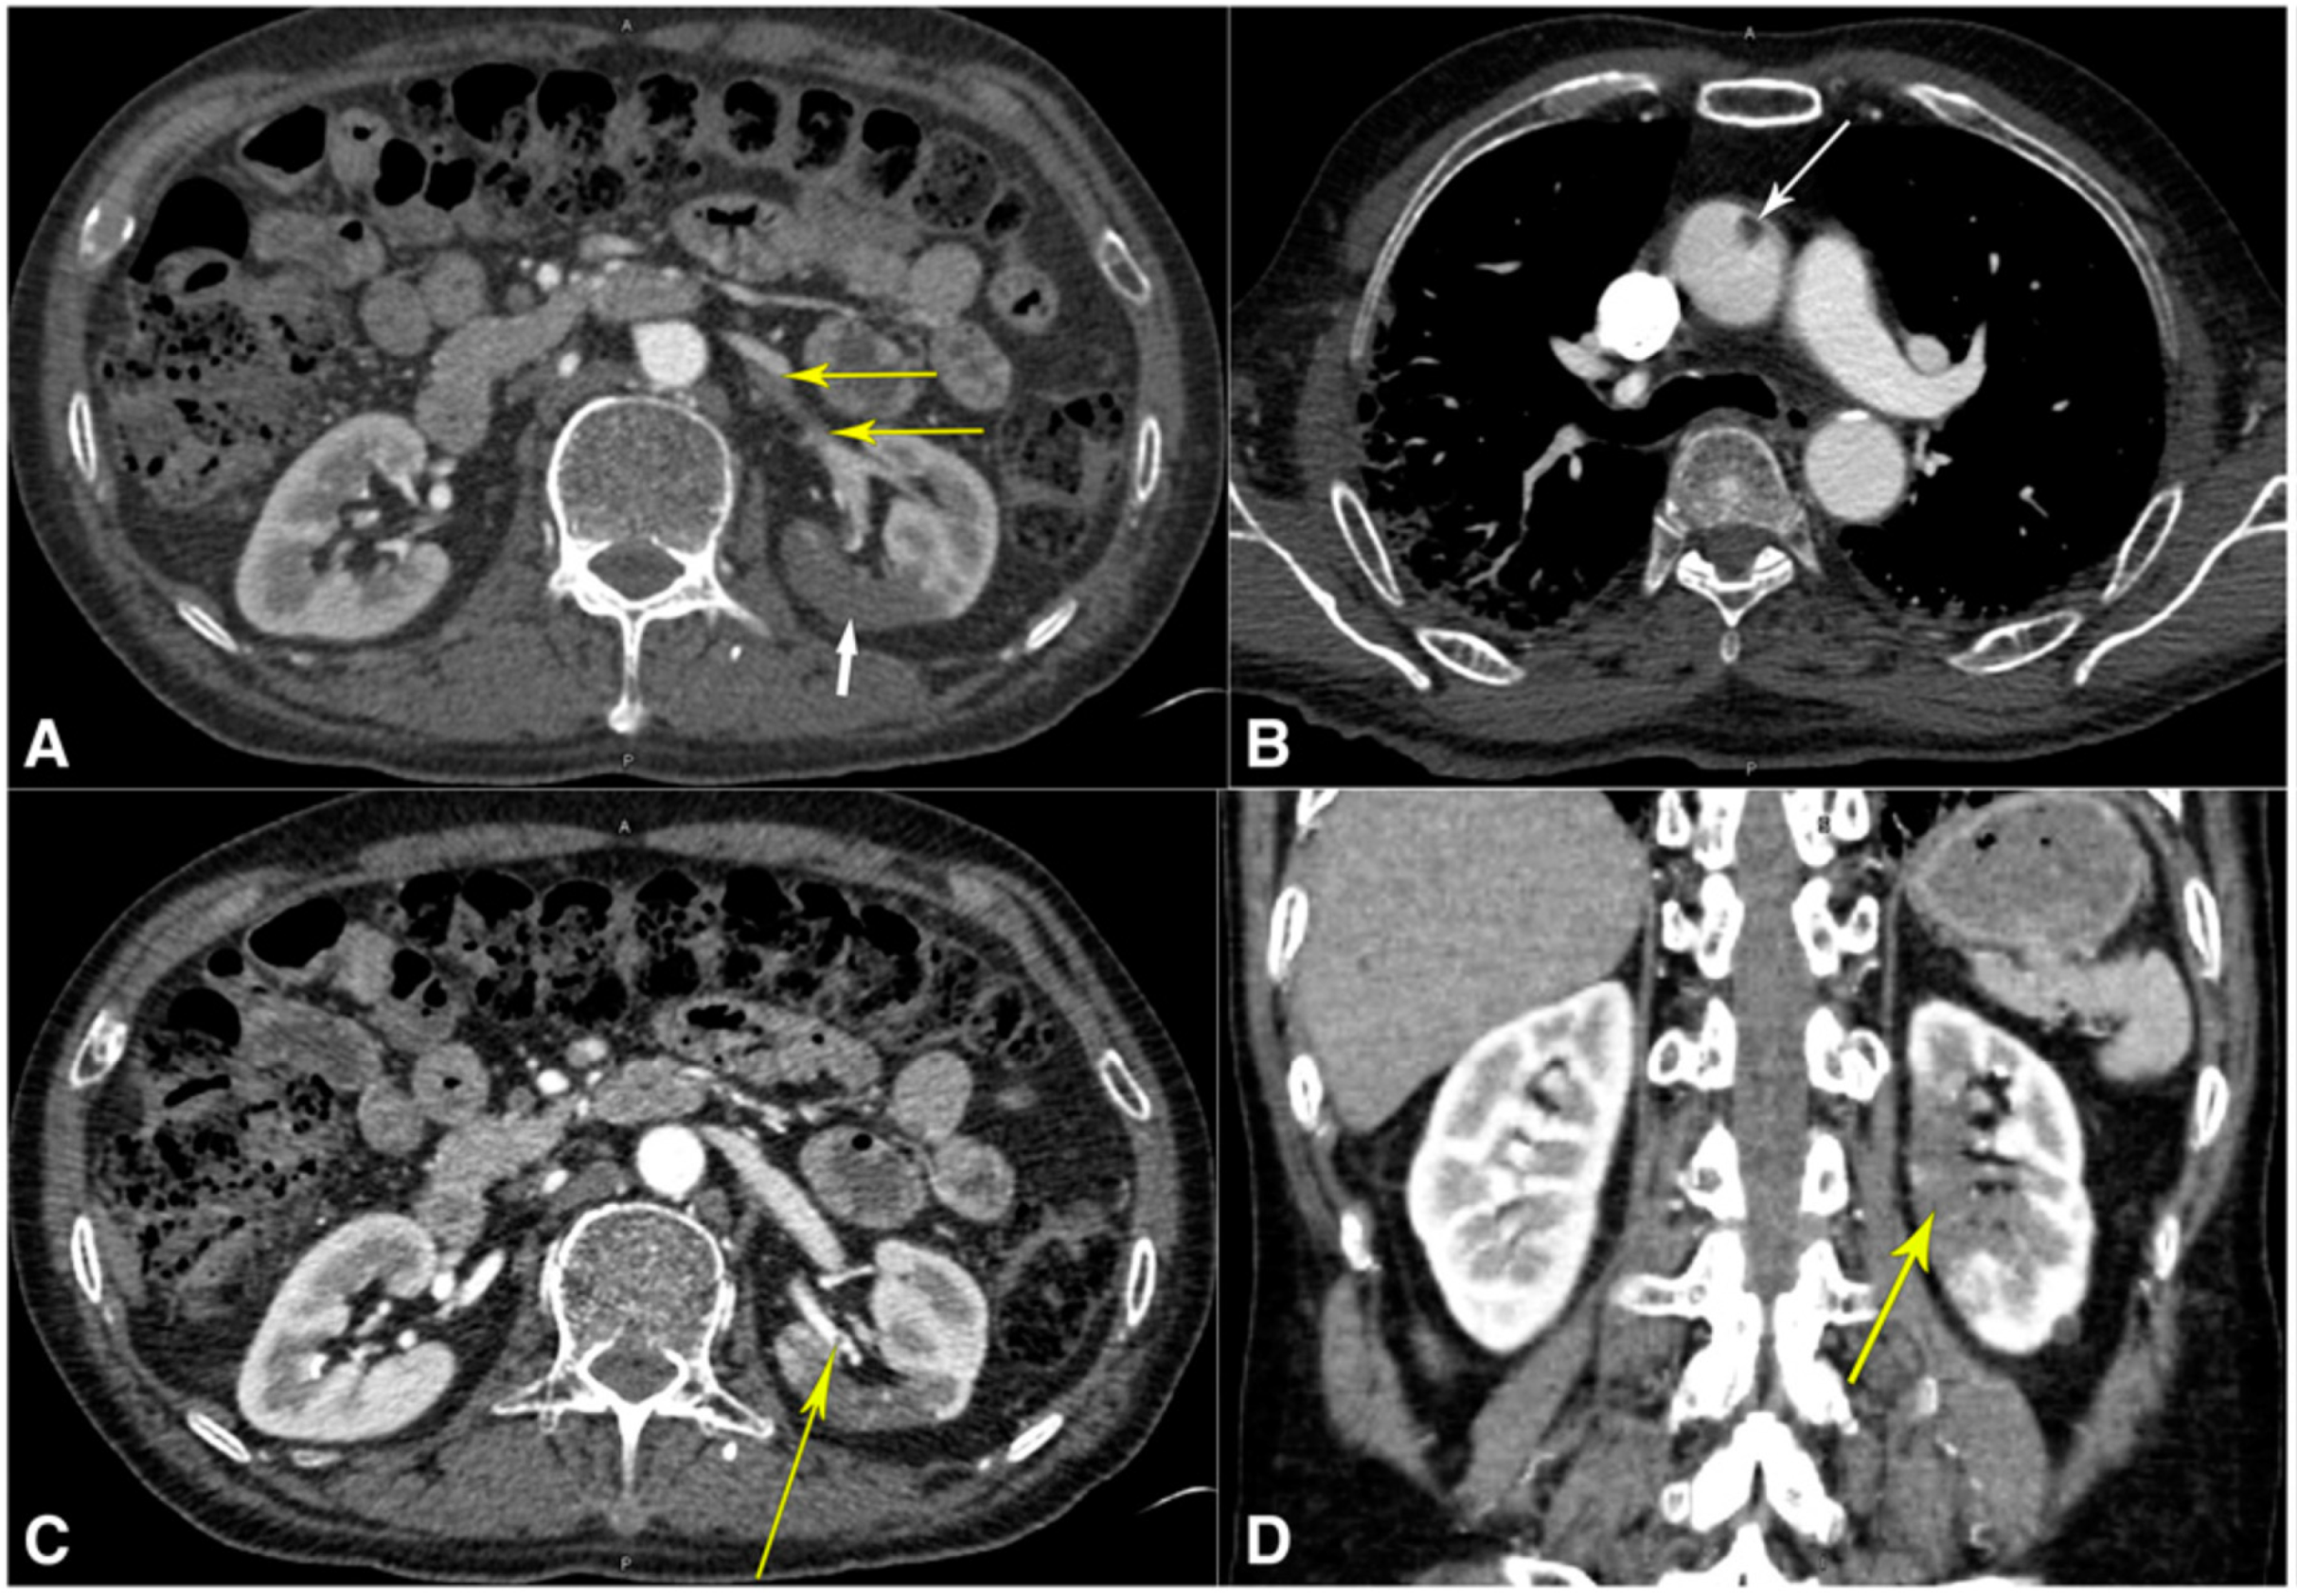

4.3.3. CT Images of the Renal Artery

| 2 | Philipponnet et al. [113] (2020) | 01 | LBBM | CVD, Diabetics | Due to increased inflammation, platelet activation, endothelial dysfunction, and stasis, COVID-19 may predispose individuals to thrombotic illness in both the venous and arterial circulation. | Renal Thrombosis | CT | NR |

| 5 | Singh et al. [116] (2020) | 01 | LBBM | Mucormycosis | Renal artery thrombosis in a COVID-19 patient led to renal infarction and nephrectomy. | Renal Artery Infarction | US | Anticoagulation |

| 9 | Lushina et al. [120] (2021) | 01 | LBBM | Hypertension | RAAS and microthrombosis leads to CKD. | Renal Thromboembolic | CT | NR |

- Lushina, N.; Kuo, J.S.; Shaikh, H.A. Pulmonary, cerebral, and renal thromboembolic disease in a patient with COVID-19. Radiology 2020, 296, E181–E183. [Google Scholar] [CrossRef] [PubMed]

- Mukherjee, A.; Ghosh, R.; Furment, M.M. Case Report: COVID-19 Associated renal infarction and ascending aortic thrombosis. Am. J. Trop. Med. Hyg. 2020, 103, 1989. [Google Scholar] [CrossRef]